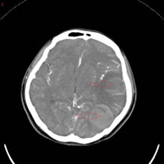

A 32-year-old woman in her 10th week of pregnancy presented to our hospital with nausea, vomiting and headache 10 days ago, increased nausea and vomiting with blurred vision and poor response 7 days ago, and yesterday developed a fever with a temperature of up to 38°C. She was admitted with a diagnosis of Wernicke’s encephalopathy combined with severe pregnancyrelated emesis. The patient had stopped menstruating 10 weeks earlier, denied oral contraceptive use, denied a family history of hereditary propensity to thrombosis, and denied a history of haematological disorders, autoimmune diseases, and intracranial and extracranial tumours. On admission, the patient’s main symptoms were persistent headache, nausea and vomiting, with normal vital signs and muscle strength. Her D-dimer level was 5.98 mg/L and β-human chorionic gonadotropin >10,000 IU/L. Other laboratory tests were essentially normal, such as routine blood, coagulation, urine, liver function, renal function and protein C. At the time of admission, the cranial CTV+CTA showed a tortuous left anterior cerebral artery segment A1, left jugular vein, left transverse sinus and sigmoid sinus thrombosis (Figure 1A), and cranial CT showed a large lamellar high-density shadow in the left temporal lobe surrounded by a lamellar low-density shadow. The diagnosis was venous sinus thrombosis combined with left temporal lobe cerebral haemorrhage (Figure 1B). He was admitted to the Intensive Care Unit(ICU) on a conservative basis, and a neurological consultation revealed poor mental health and limb weakness (4/5), with no other focal neurological deficits identified. After 3 days of conservative treatment, symptoms of drowsiness, blurred vision and impaired consciousness developed and CT showed an increase in the area of blood accumulation in the right ventricle (Figure 1C). An emergency mechanical thrombectomy was performed, after which the occluded left transverse and sigmoid sinuses were successfully recanalized and the haemorrhagic focus did not continue to increase in size (Figure 1D). Due to the presence of some residual thrombus, she continued postoperative LMWH therapy and urokinase thrombolysis, after which she was discharged in a stable condition with significant improvement in her symptoms. At the 1-month follow-up after discharge (Figure 1E), no recurrence of the disease was noted.

Figure 1A & 1B: Tortuous left anterior cerebral artery segment A1, left jugular vein, left transverse sinus and sigmoid sinus thrombosis.venous sinus thrombosis combined with left temporal lobe cerebral haemorrhage.